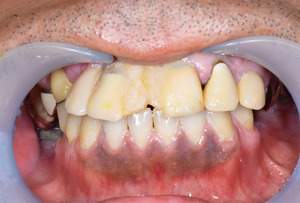

BEFORE

AFTER

| 年齢・性別 | 63歳・男性 |

|---|---|

| 主訴 | インプラントがしたい |

| 治療内容 | オールオン4(上顎) |

| 治療費 | オペ料金(仮歯・薬代金含み)150万円+上部構造 (ハイブリットセラミック)150万円=計300万円(消費税別) |

| 治療期間 | 7ヶ月 |

| リスク・副作用 | 治療後の口腔管理が不適切な場合、インプラント周囲に炎症が生じインプラントが脱落する恐れがある。 |

審美的にも、機能的にも調和がとれており何よりも食べ物がちゃんとかめると言う事に感激されておりました。 今後定期検診をしながら経過を診て行きたいと思い

ます。